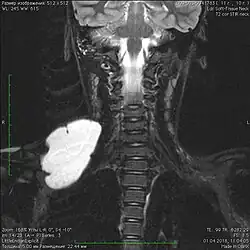

Пороки развития лимфатических сосудов в области головы и шеи чаще всего определяются при рождении или в первые годы жизни ребёнка, в возрасте до одного года в 60-80 % случаев[6]. Основными методами визуализации лимфатической мальформации являются ультразвуковое исследование (УЗИ) и магнитно-резонансная томография (МРТ). Данные исследования позволяют определить площадь и объём патологических тканей, размеры кист, топографию образования.

В литературе приводится множество наблюдений различных локализаций общих (кистозных) лимфатических мальформаций. Описаны следующие области: голова и шея, нижние конечности, средостение, матка, поджелудочная железа, мошонка, твёрдая мозговая оболочка, оболочки яичка, сердце. В 50-75 % лимфатические мальформации встречаются в области головы и шеи[10][11], в 27 % они встречаются в области туловища, в 24 % — на конечностях. Висцеральные лимфатические мальформации определяются очень редко[12][13].

Лимфатические мальформации в области головы и шеи, диагностируемые внутриутробно, обычно имеют огромные размеры, угрожающие жизни матери и ребёнка. В связи с этим заранее формируется специальная бригада врачей для оказания реанимационных мероприятий, в частности для предотвращения острой дыхательной недостаточности у новорождённого. За рубежом комплекс данных мер носит название EXIT (The ex utero intrapartum therapy procedure)[16].